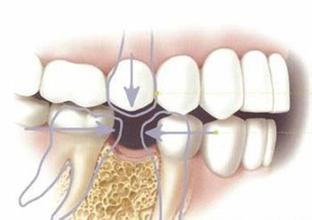

再想起网上描述的拔牙更是四肢无力:打麻药、牙肉切开、锤子敲分牙齿、拔出、缝合。打三天吊针、脸会肿、无法说话、只能吃流质食品......想想就冒冷汗!

终于,两腿颤抖的走进医院,切割的时候还没什么感觉,最痛苦的是分牙!小锤子像钉钉子似得,在你嘴里一阵狂敲,震得半个脑袋都痛。虽然打了麻药,可拔牙出来的时候,那个味道......可能开始麻药只打进了一半,还没缝合就开始痛了,于是我又挨了一针!小弯钩针在牙肉上穿来穿去,就像缝衣服一样,但感觉就......